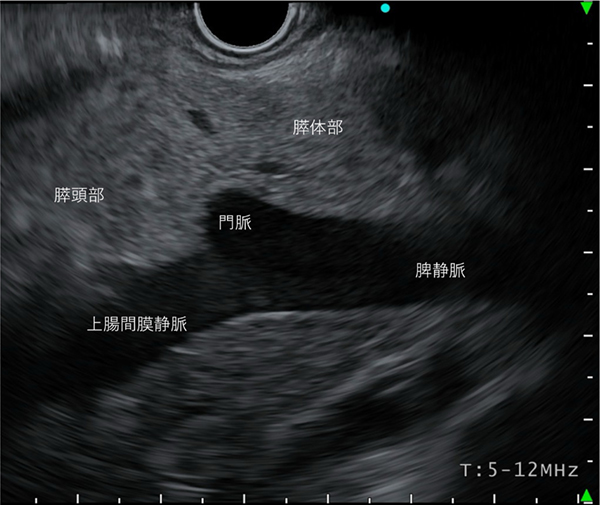

〈胃内操作による観察〉

脾静脈を描出し、静脈を追いかけるように観察します。自然とその上側に膵臓(体部と尾部)が描出され、観察可能となります。